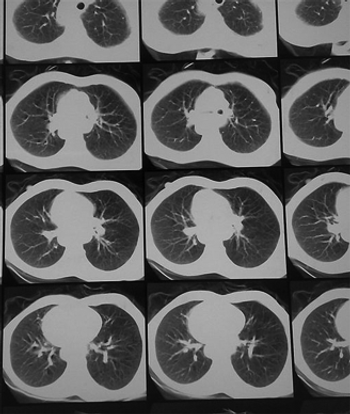

Annual screening of people at high risk for pancreatic ductal adenocarcinoma (PDAC) because of CDKN2A mutations was relatively successful and allowed for the detection of disease in time to perform surgery.